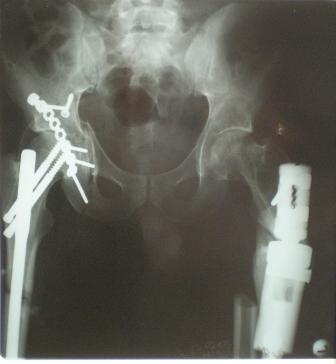

Глубокоуважаемые коллеги! Благодарю за полезные советы, которые нам

очень помогли в выборе оперативной тактики пациента. 13.02.08 мы

выполнили первый этап оперативного лечения этого больного. Вначале

зафиксировали левое бедро АВФ Гофмана

(главный травматолог области достал из каких-то "анналов", первый раз в

жизни увидел этот аппарат вживую). После наложения "ДРУ Челнокова"

выполнили ЗИО правого бедра реконструктивным штифтом Chm. Далее уложили

пациента на левый бок и выполнили остеосинтез вертлужной впадины.

Ограничились задне-латеральным доступом без отсечения вертела, чтобы не

утяжелять операцию. Результат прилагается.

Следующим этапом планируем выполнить ЗИО левого бедра.

Но есть еще вопросы:

1.	укорочение левой н\конечности составляет 3 см. Необходимо ли думать

об этом сейчас, или вернуться к устранению укорочения после консолидации

перелома?

2.	сохраняется некоторое смещение переднего отдела вертлужной впадины,

нужно ли его устранить?